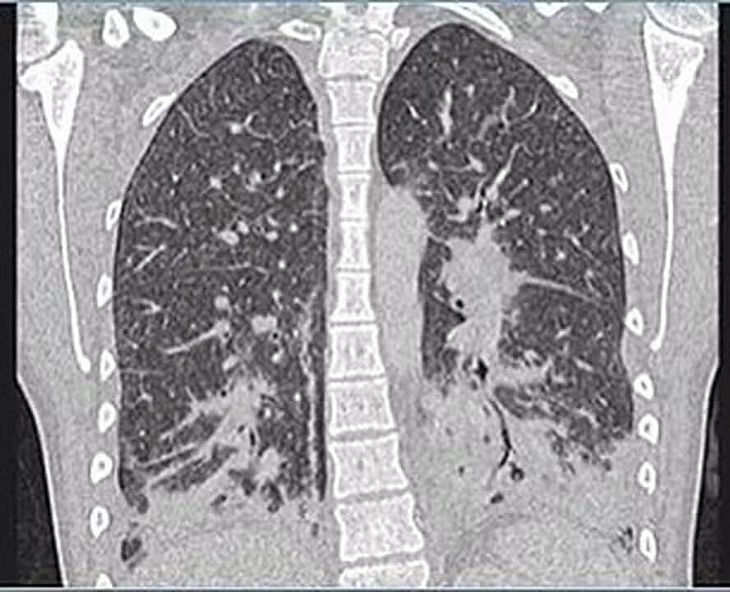

As imagens dos exames mostravam que a jovem tinha opacidades de vidro, geralmente ocorre junto com a consolidação nos pulmões. Consolidação se refere ao espessamento ou inchaço do tecido pulmonar, que acontece quando os espaços de ar nos pulmões se enchem de fluido, pus, sangue ou células.

Ela foi inicialmente diagnosticada com pneumonia bacteriana grave, que foi tratada com antibióticos por cinco dias, porém, devido a não melhora dos sintomas, os médicos realizam um exame de raio-x que indicou manchas translúcidas por todos os pulmões, sugerindo que eles estavam cheios de líquido e apresentavam sinais de danos nos tecidos.